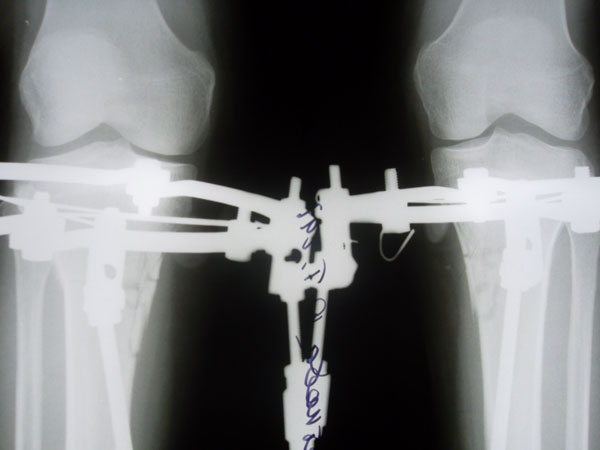

Я приехала 1 марта, сдала анализы, 2 марта ноги мои сломали) На следующий день Малиновка и Жасмин притащили ходунки и Жасмин так спокойно сказала-вставай...У меня аж все похолодело от страха, но встала..Все-таки нашатырь-классная вещь!!)))Постояла несколько секунд-и в койку...Трясло от слабости..Больновато, конечно, было, но терпимо,может уколы еще влияли..На след день сделала пару шагов сама, потом дошла до раковины..Ну, а когда поджало (имею в виду жуткое желание побыть в туалете одной